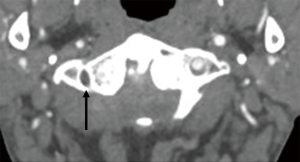

All the images were reviewed in consensus by three radiologists, each of whom had at least ten years of experience in CT diagnosis. By consulting the three-section classification criteria of V3 (13,28), we divided V3 into three subsegments: vertical portion originating from the foramen of C2, horizontal portion originating from the foramen of C1, and extradural portion originating from the posterior atlantooccipital membrane and ending at the site of piercing the dura. The three subsegments were referred to as V3v, V3h, and V3e, respectively (Figures 1-4). The number of branches was recorded. With regard to the arrangement of the branch of V3, the number 0 indicated no branches in the subsegment, and the number 1 indicated no less than one branch in the subsegment (Figure 1). There were eight kinds of arrangements of the branches altogether (000; 100; 110; 111; 010; 011; 001; 101). After an agreement was reached by consensus, all the data were confirmed. The reproducibility was assessed by comparing a subset of measurements made on 100 randomly selected cases. The radiologists were blinded to the measurements taken by the other radiologists. The 100 cases were reviewed by three observers, and interobserver agreement was calculated. All the data were imported into R statistical software, version 3.6.1, to be processed further.

Six, 8, and 7 cases were not shown in the left V3v, V3 h, and V3e, respectively, among the 668 cases. On the left, 25% (167/662), 20.21% (135/660), and 6.59% (44/661) were the frequencies of one branch in the V3v, V3h, and V3e, respectively, and 1.05% (7/662), 0.00% (0/660), and 0.45% (3/661) were the frequencies of two branches, respectively. Fourteen, 15, and 15 cases were not shown in the right V3v, V3 h, and V3e, respectively, among the 668 cases. On the right, 25.04% (167/654), 17.07% (114/653), and 6.44% (43/653) were the frequencies of one branch in the V3v, V3h, V3e, respectively, and 1.04% (7/654), 0.3% (2/653), and 0.15% (1/653) were the frequencies of two branches, respectively (Table 2).

The vertebral artery has a tortuous shape to meet the need for flexible movement and to facilitate smooth blood flow. V3 is anatomically defined as the vertebral artery that passes from the foramen of C1 to the site of the piercing dura, and it is radiologically defined as the artery passing from the foramen of C2 to the piercing site (26,27). Considering the occipito-atlantoaxial complex is a functional complex, we adopted the latter definition. The V3 that was identified was then divided into two portions demarcated by the foramen of the C1 process, namely, the horizontal and vertical portions, as reported in previous studies. In this study, we divided V3 into three subsegments, namely, the V3v, V3h, and V3e subsegments (13,29). V3e was the section passing from the posterior atlantooccipital membrane to the site of piercing the dura (28). The V3v was easily identified on CTA images. The starting point of V3e was defined as the point of intersection of the course of V3 and the superior border of C1 to which the posterior atlantooccipital membrane attached (29). The terminal point of V3e was marked by the density difference between the cerebrospinal fluid and dura mater on CTA images. The branch arising from V3h was defined as the suboccipital artery of Salmon that supplied the neighboring muscles. The frequency of the artery of Salmon was 20% in a study of 10 cadavers and 67% a study of 15 cadavers (26,27). The frequency of the artery of Salmon was 17.07–20.21% in V3h. Our results are consistent with those reported by Tubbs RS et al. Three branches arising from the V3h were discovered by dissecting cadavers (27), while no more than 2 branches were revealed in our research. The frequency of the branch was 25% in V3v and less than 6% in V3e. The rate of asymmetry in the arrangements of the branches of V3 was 30% according to the autopsy; in other words, the rate of symmetry was 70% in the arrangements (27). In our study, all eight arrangements of branches of V3 were symmetric, regardless of the sex and side of the patient. The permutation of (0,0,0) was the most frequently occurring permutation, followed by (1,0,0), and (0,1,1) was the least frequent (Table 3).